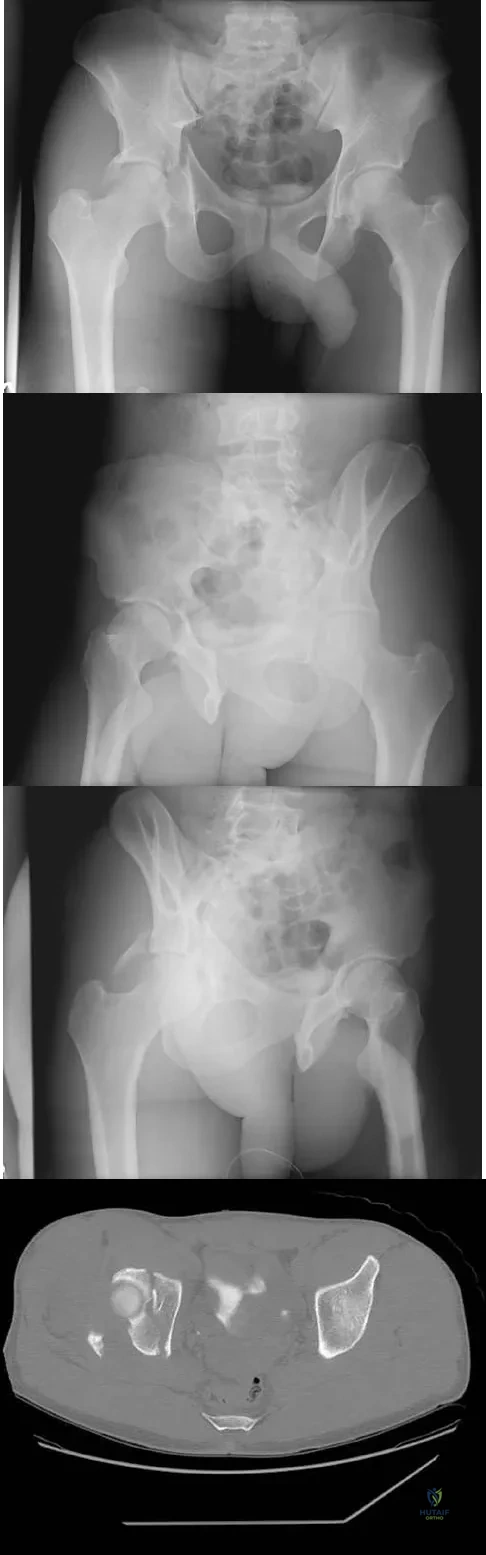

The radiographs and CT scan seen in Figures 28a through 28d reveal what type of acetabular fracture pattern?

Explanation

The AP, obturator oblique, and iliac oblique views of the pelvis reveal a fracture that disrupts the iliopectineal and ilioischial lines, indicating a fracture that involves both anterior and posterior columns. However, it does not have the other features of anterior or posterior column fracture patterns. A displaced posterior wall fracture is also present, best seen on the obturator oblique view. The anterior to posterior directed fracture line on the CT scan indicates a transverse fracture; therefore, the patient has a transverse with posterior wall fracture pattern. A T-type fracture would be similar but would have a break into the obturator ring. Tile M: Describing the injury: Classification of acetabular fractures, in Tile M, Helfet DL, Kellam JF (eds): Fractures of the Pelvis and Acetabulum, ed 3. Philadelphia, PA, Lippincott Williams & Wilkins, 2003, pp 427-475.